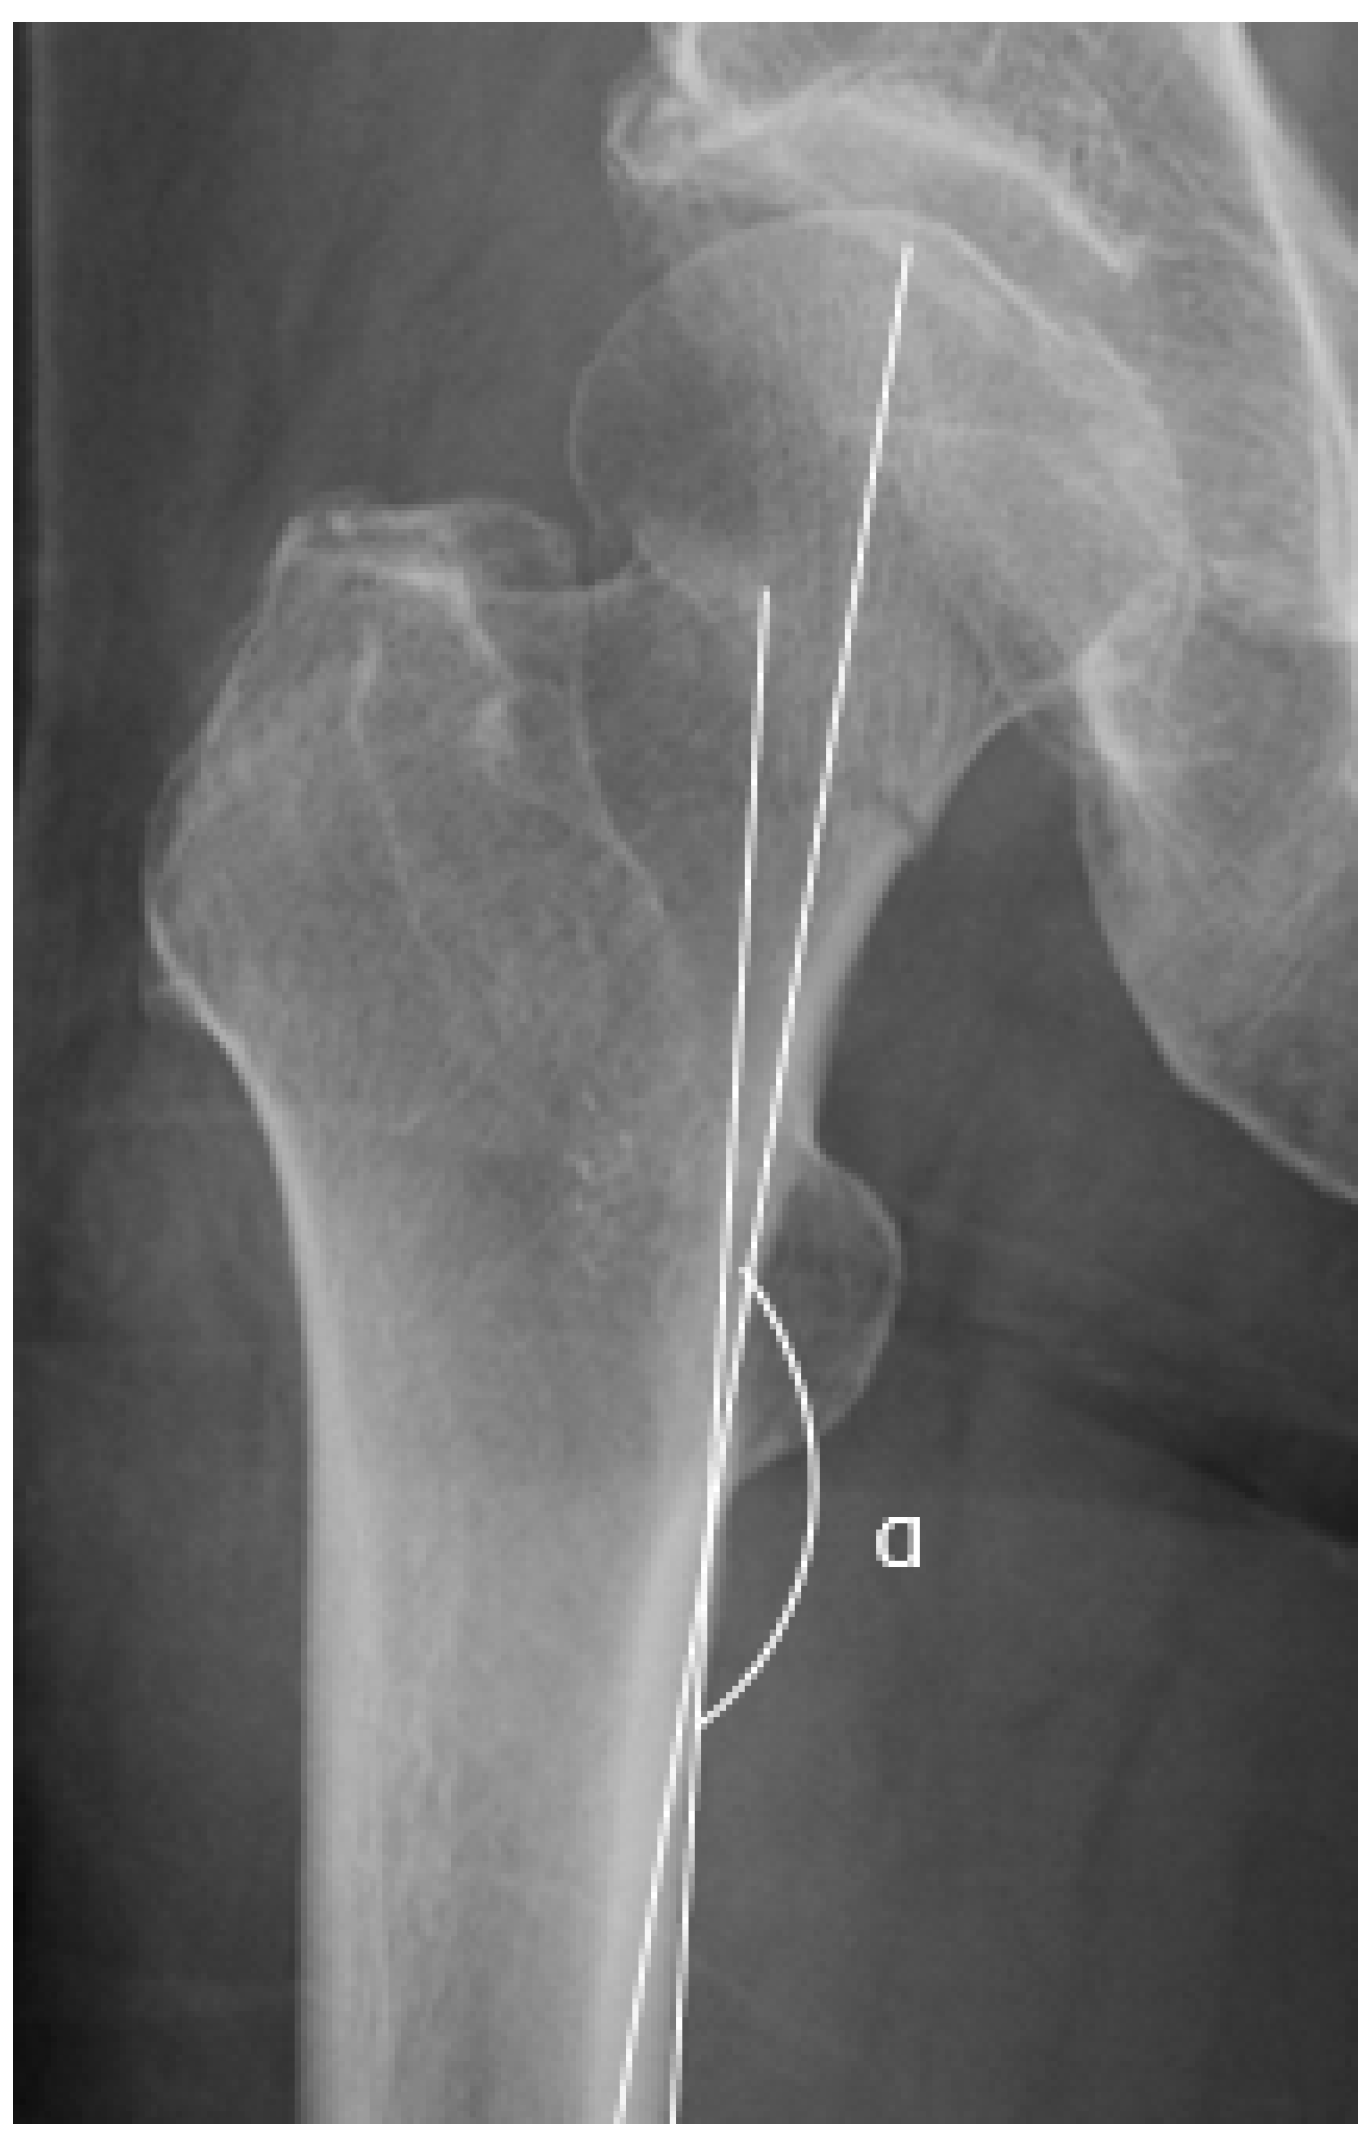

2.3. AP Hip Radiographs

2.4. Radiographic Measurements

2.5. Garden Alignment Index

2.6. Valgus Tilt Measurement